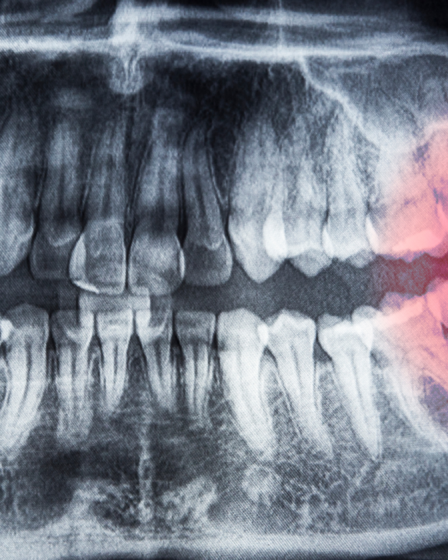

Bucomaxilo no Tatuapé: Riscos do Siso Incluso e Quando Extrair

A chegada dos terceiros molares, conhecidos como dentes do siso, costuma gerar apreensão em muitos jovens e adultos. Infelizmente, nem sempre esses dentes encontram espaço suficiente na arcada dentária para nascerem corretamente. Nesse sentido, contar com a avaliação de um especialista em bucomaxilo no Tatuapé é fundamental para identificar se o dente está incluso ou …